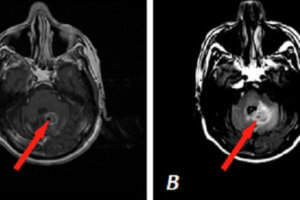

Tumor in the CPA

Vestibular Schwannoma

Vestibular schwannomas are benign extra-axial neoplasms that result from proliferation of the schwann cells associated with the eighth (vestibulo-auditory) cranial nerve. The commonly arise in the cerebellopontine angle and may extend along... Read more »